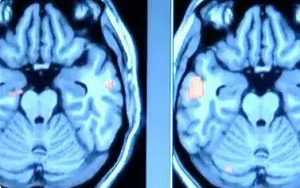

每个人都有着强大的力量,也许只是你还未挖掘自己的潜能。在大脑中搜寻过去发生的事情是我们最神奇的能力,虽然记忆像呼吸空气一样,稀松平常,但事实上我们不了解它,这种能力的背后隐藏着很多奥秘。BBC纪录片《记忆的奥秘》带你一起走进神奇的世界。记忆能够塑造人生,你的记忆就代表你自己。

记忆,孩提时代就有,步入成年之后,记忆力更加重要,随着时间的流逝,记忆又有着怎样的秘密呢?记忆力是与生俱来的,然而这种能力又常常被忽略,但是一旦丧失,后果严重。但是你了解记忆吗?事实上是,即使你不了解记忆的机制,记忆也会自己产生。